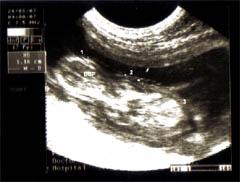

Poza Examen Ecografic

Permite stabilirea diagnosticului de certitudine în unele situaţii cum ar fi:

Aparatul ecografic permite realizarea ecografiilor la domiciliul clientului